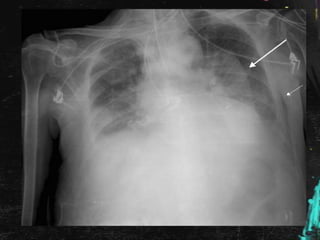

Rx de tórax en planta:

Se comenta el caso al Radiólogo, quien informa

que se trata de una falsa imagen

provocada por pelo largo recogido en moño

o coleta, por lo que es dada de alta con

seguimiento en consulta externa de Medicina

Interna con Rx de Tórax y analíticas; por la

presencia de imagen de vidrio deslustrado en

el TAC poco valorable por la escasa

inspiración de la paciente.

En este caso : Tenía pañuelo que ocultaba el

pelo duro, denso y espeso.

Al realizar la radiografía de tórax:

• Cuello en hiperextensión.

• Densidad del «moño»

Rx de tóraxen planta:

Se comenta elcaso al Radiólogo, quien informa que se trata de una falsa imagen provocada por pelo largo recogido en moño o coleta, por lo que es dada de alta con seguimiento en consulta externa de Medicina Interna con Rx de Tórax y analíticas; por la presencia de imagen de vidrio deslustrado en el TAC poco valorable por la escasa inspiración de la paciente.

Inmigrantes: • Cultura eIdioma. • Hábitos peculiares. • Enfermedades endémicas. En este caso : Tenía pañuelo que ocultaba el pelo duro, denso y espeso. Al realizar la radiografía de tórax: • Cuello en hiperextensión. • Densidad del «moño»